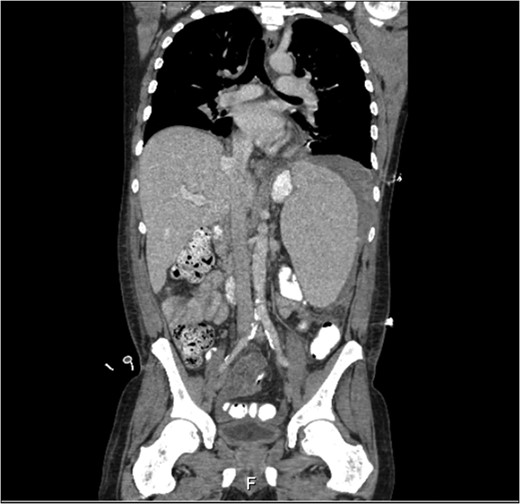

Ultrasonographic examination showed two hemangiomas in the liver and free fluid arount the liver. The spleen was surrounded by free fluid and showed a largely homogeneous aspect with on the cranial side an inhomogeneous echogenic area. Computed tomography confirmed free intra-abdominal fluid and showed hepatosplenomegaly with an intracapsular splenic rupture with probable leakage of blood to the abdominal cavity (Fig. 1).

Computed tomography of the abdomen showing hepatosplenomegaly with free fluid around te spleen.